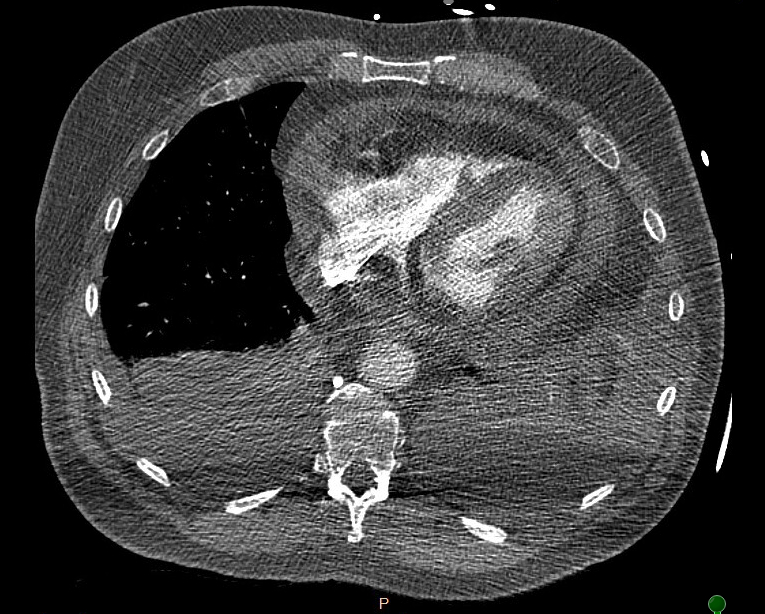

Abstract Body (Do not enter title and authors here): Case Description: A 71-year-old male presented to the hospital for dyspnea and chest discomfort for the past 2 weeks. He has a history of AAA status post stent and current tobacco use with emphysema. On admission, he was found to be tachycardic with rates reaching as high as 180 with systolic blood pressure of 89/61 and hypoxic with SpO2 of 80%. EKG revealed AFib with RVR with no acute ischemic changes. Troponins were negative and proBNP was 307. Infectious workup was negative. CTA chest showed no evidence of PE or dissection, however, moderate pericardial and bilateral pleural effusion was shown with mediastinal lymphadenopathy. After starting an esmolol and amiodarone drip, he converted to sinus tachycardia. TTE showed an EF 55%, echo dense debris measuring 2 cm with 1 cm effusion within the pericardial space resulting in significant compression of RA and RV. Findings were concerning for tamponade evidenced by invagination of RA and RV during systole and diastole respectively and greater than 50% variation and tricuspid inflow velocities with respiration. He was taken emergently to the OR for a pericardial window, thoracentesis, and chest tube. 300 mL and 400 mL of cloudy straw-colored fluid were removed from the pericardial and pleural space respectively. Fluid studies were negative for malignant cells and cultures remained negative. Repeat TTE showed an EF 55%, with epicardial fat pad and small posterior pericardial effusion. ANA testing was positive; however, other autoimmune studies are negative. His symptoms improved and he was discharged home.

Discussion: Cardiac tamponade is commonly caused by large pericardial effusions. Mild pericardial effusion less than 1 cm on TTE does not typically cause symptoms. However, the presence of significant pericardial debris can be problematic with minimal pericardial effusion. In this case, the patient developed cardiac tamponade complicated by AFib with RVR. Fortunately, hemodynamics and symptoms improved post pericardial window draining 300 mL of bloody fluid, but the diagnosis remains unknown given negative fluid studies. It's postulated that the debris is inflammatory in nature, but the absence of a diagnosis puts the patient at high risk for shock if the pericardial window fails. Patients with pericardial debris up to 2 cm on TTE with risk of developing pericardial effusion should be monitored with follow up TTE. Further studies are necessary to unveil the underlying etiology of large pericardial debris.